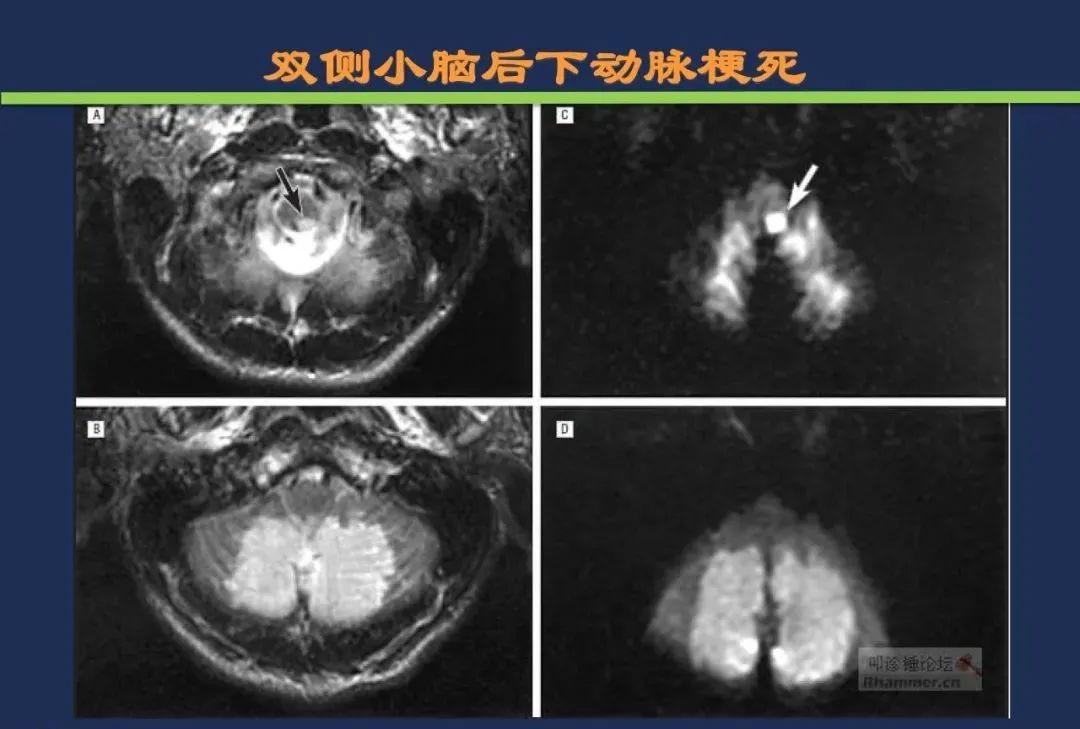

小脑后下动脉